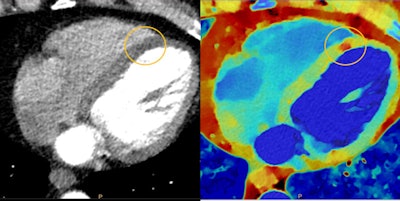

Myocardial perfusion defects are difficult to visualize on conventional CT (left) due to beam-hardening artifacts, but they are visible on spectral CT (right). Image courtesy of Philips Healthcare.

Myocardial perfusion defects are difficult to visualize on conventional CT (left) due to beam-hardening artifacts, but they are visible on spectral CT (right). Image courtesy of Philips Healthcare.The general idea of the technology is that by acquiring images at different energy levels, spectral CT can be used to differentiate between different types of tissue, such as a malignant lesion from benign tissue. But the advancement of the technology has been slowed by perceptions that it's more difficult to perform than conventional CT.